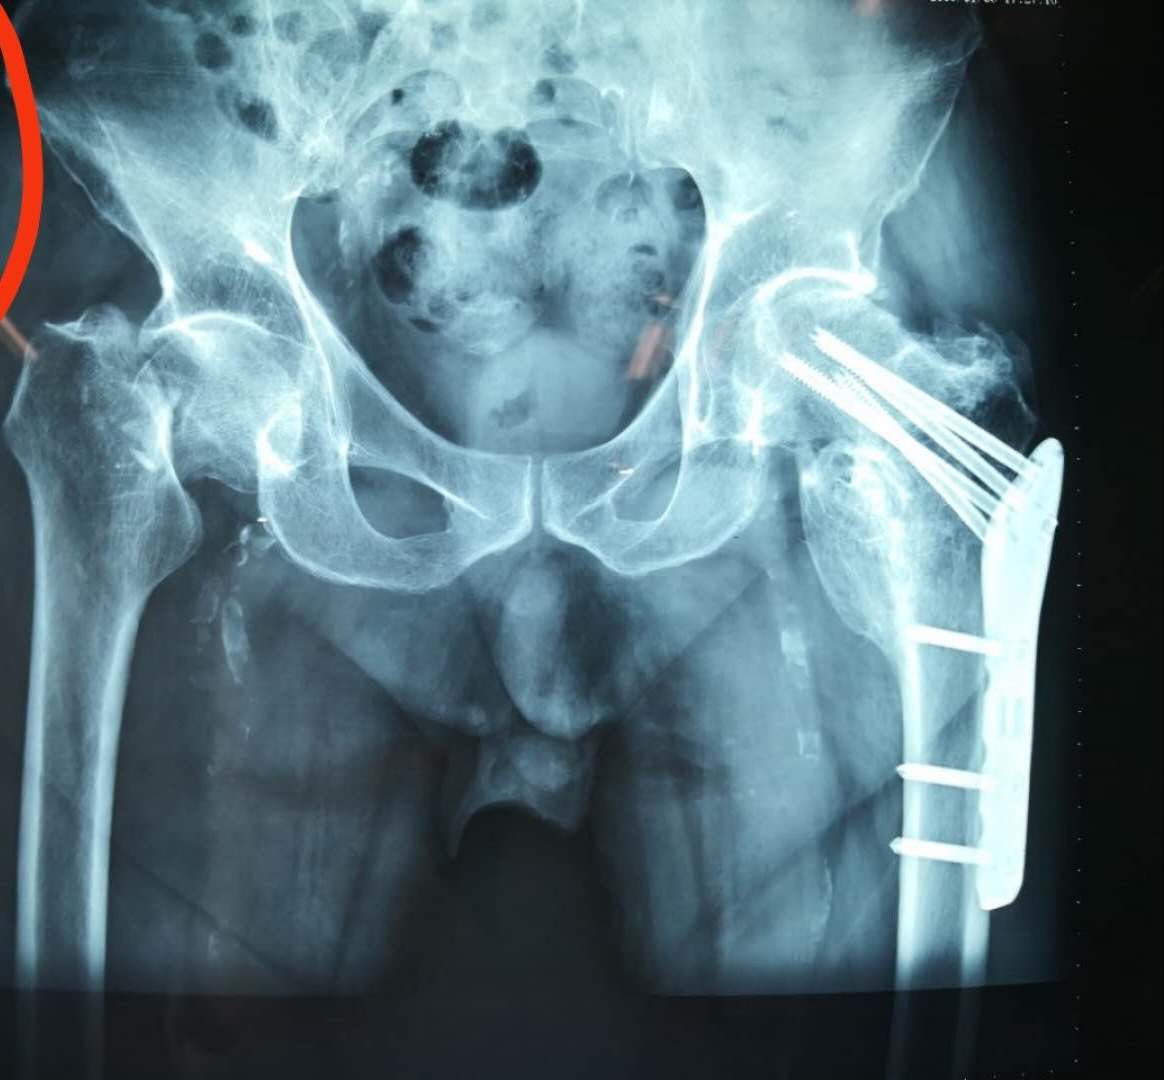

(术前)

伤情并不乐观,左侧股骨颈骨折,Ⅲ型及左侧锁骨远端骨折。虽然患者上肢骨折可以选择保守治疗,但下肢平时经常行走,股骨颈骨折不治?回家卧床?行吗?